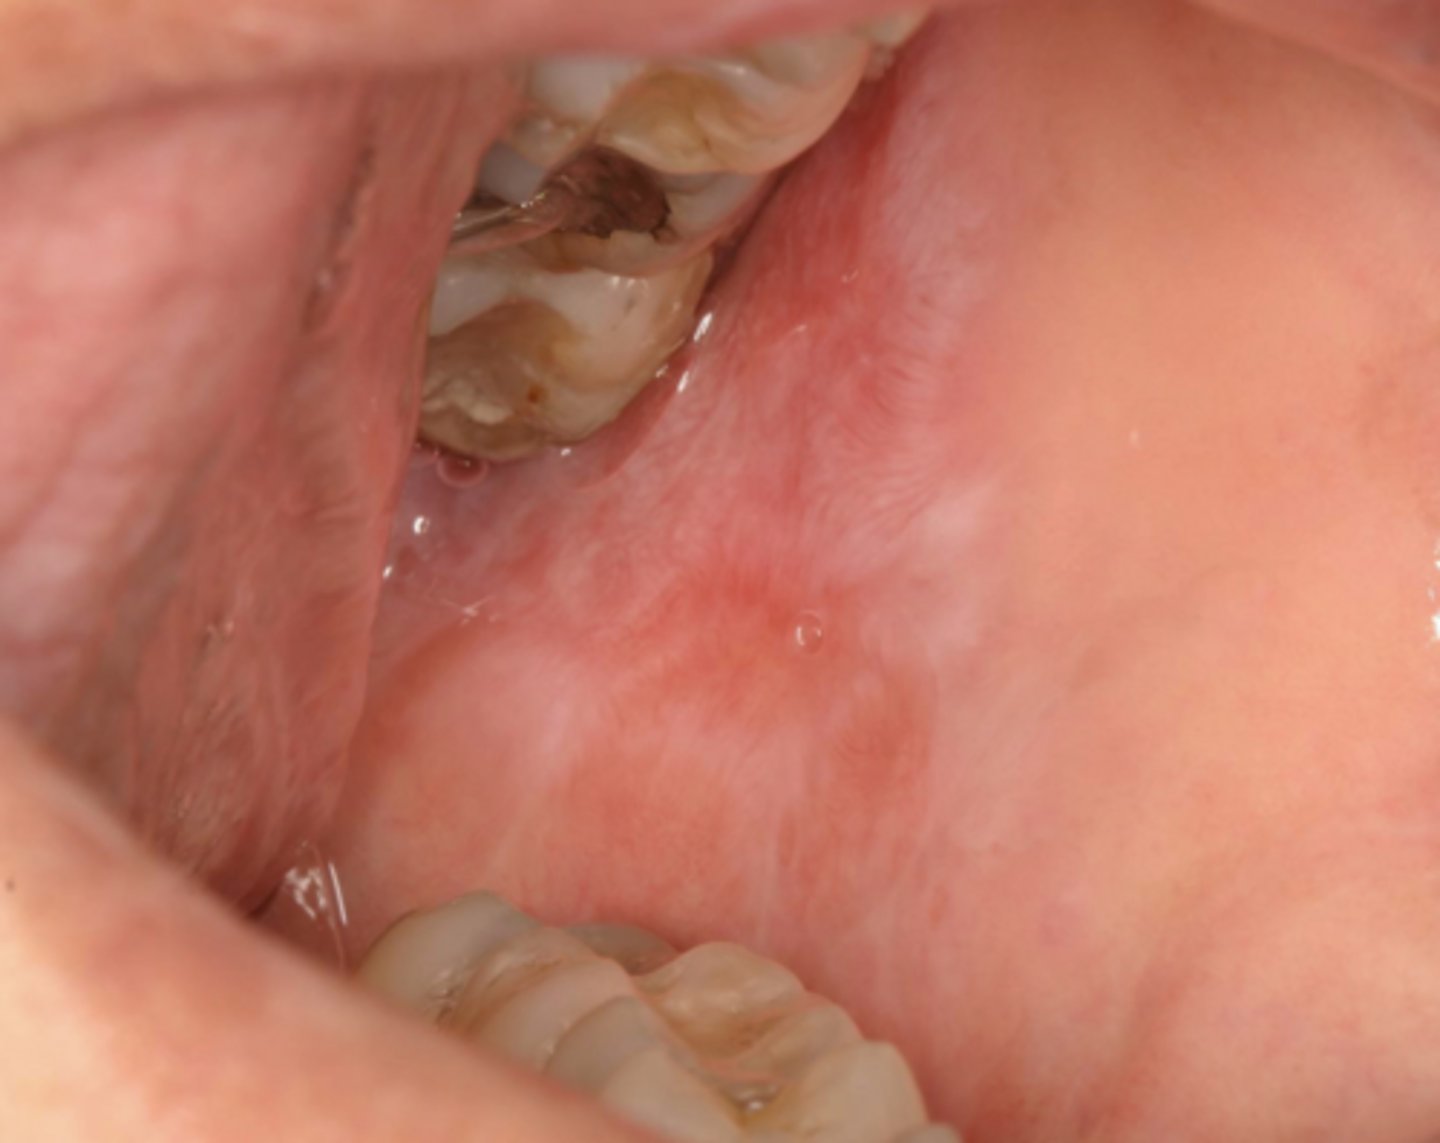

lichen planus (erosive/erythematous)

What type of lichen planus?

- Often symptomatic

- Striae at periphery of erythema

- May cause desquamative gingivitis

- Must be distinguished from mucous membrane pemphigoid or pemphigus

What condition?